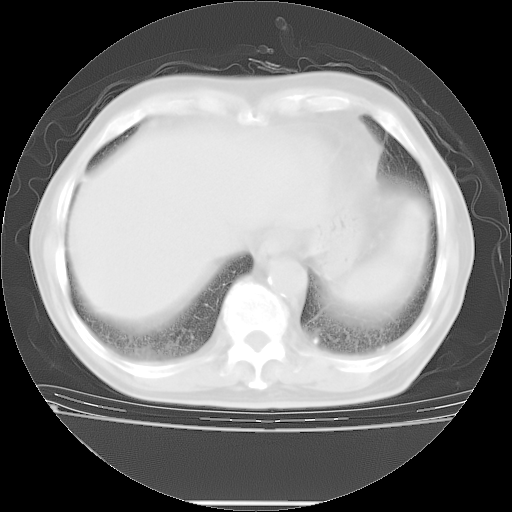

今天复查肺部CT,发现双肺广泛磨玻璃样改变。所以我把3月19日和5月9日相隔50天的肺部CT上传。请大家会诊。

2009年3月19日肺部CT片。

2009年3月19日肺部CT